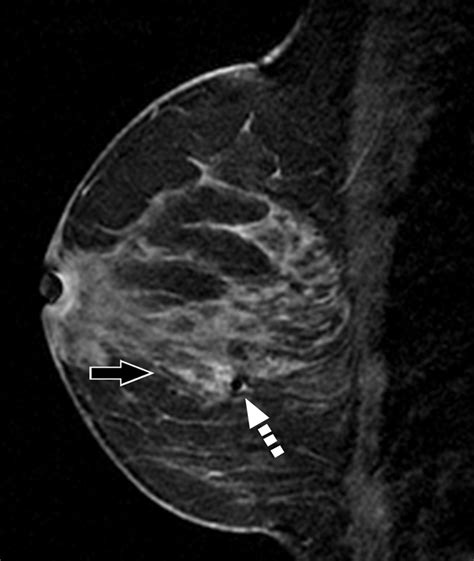

• Mammogram findings: ADH often appears as suspicious microcalcifications (tiny calcium deposits) on a mammogram.

• Enhanced Surveillance: You may undergo more frequent breast imaging, such as alternating every six months between a mammogram and an MRI of the breast.